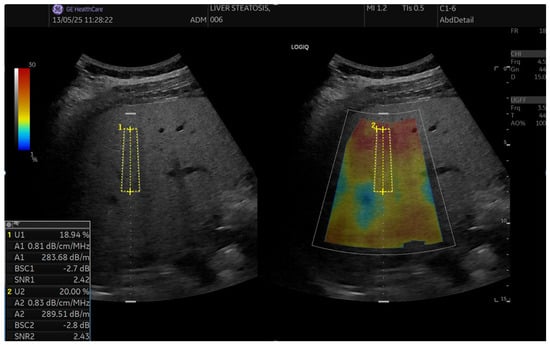

SNR is another novel QUS parameter. It quantifies the homogeneity of B-mode image texture. SNR is known as a parameter of the Rayleigh distribution and is defined as the reciprocal of the Rayleigh parameter. In a normal healthy liver, the texture of B-mode images is not homogeneous due to the presence of structures such as blood vessels. On the contrary, in severe fatty liver, fat droplets become the dominant scatterers and mask these structures, resulting in a more homogenous texture. Consequently, SNR increases with the amount of fat droplets and the homogeneity of B-mode image texture. SNR is the ratio of the average and the standard deviation of the linear amplitude. The linear amplitude is calculated using tissue-harmonic B-mode data acquired under fixed transmission and reception conditions—Figure 1 and Figure 2.

Figure 1. Continuous scan sequence for fundamental and tissue-harmonic B-mode base data. Fundamental frames are used to estimate the attenuation coefficient (AC) and integrated backscatter coefficient (BSC), while tissue-harmonic frames are used to compute the signal-to-noise ratio (SNR). All frames are acquired in a single interleaved sequence with fixed transmit/receive settings, enabling quantitative outputs that are subsequently integrated on-system to yield the ultrasound-guided fat fraction (UGFF).

Figure 2. Example of UGFF acquisition. A homogeneous ROI (yellow) is placed in the right hepatic lobe ≥2 cm below the capsule, avoiding vessels. The system reports UGFF (%), attenuation coefficient (AC, dB/m or dB/cm/MHz), integrated backscatter coefficient (BSC, dB), and signal-to-noise ratio (SNR); the per-subject result was the median of 10 valid measurements per breathing condition.